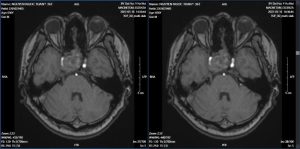

Chụp MRI sọ kiểm tra phát hiện tổn thương nhồi máu não bán cầu não phải.

Hình ảnh MRI sọ (19/05): Tổn thương ở thùy trán, thùy thái dương và thùy đỉnh phải thuộc vùng cấp máu của động mạch não giữa phải, gây hiệu ứng khối nhiều xung quanh. Trên chuỗi xung mạch TOF, động mạch cảnh trong phải nhỏ, bị đè ép bởi khối u, không thấy tín hiệu dòng chảy ở đoạn siphon động mạch cảnh trong, động mạch não giữa phải đoạn M1 nhỏ, các đoạn còn lại động mạch não giữa không thấy hẹp tắc.